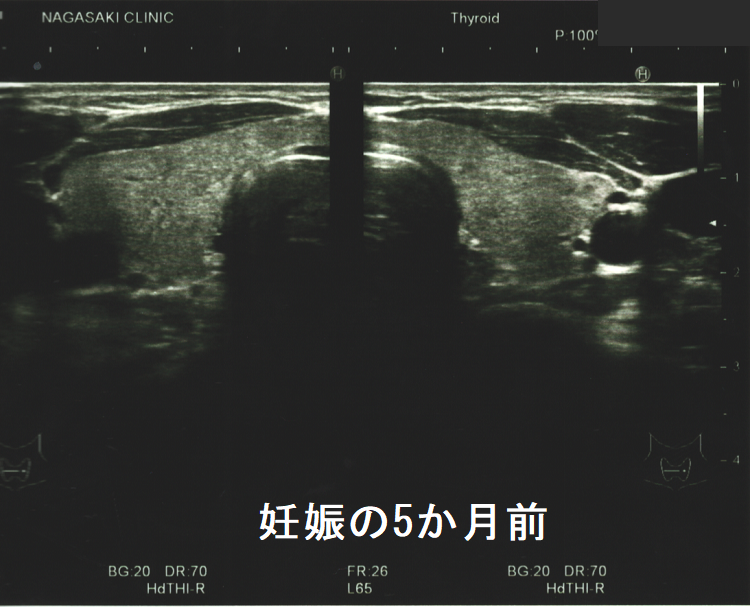

妊娠前の甲状腺超音波(エコー)検査ではなかったのに、出産後に甲状腺微小乳頭癌が見つかるケースがあります。甲状腺刺激作用を持つhCG[J Clin Endocrinol Metab. 1991 Oct;73(4):824-31.][Obstet Gynecol. 1990 May;75(5):775-8.]が、隠れていた甲状腺乳頭癌細胞の増殖を促進した可能性が考えられます。